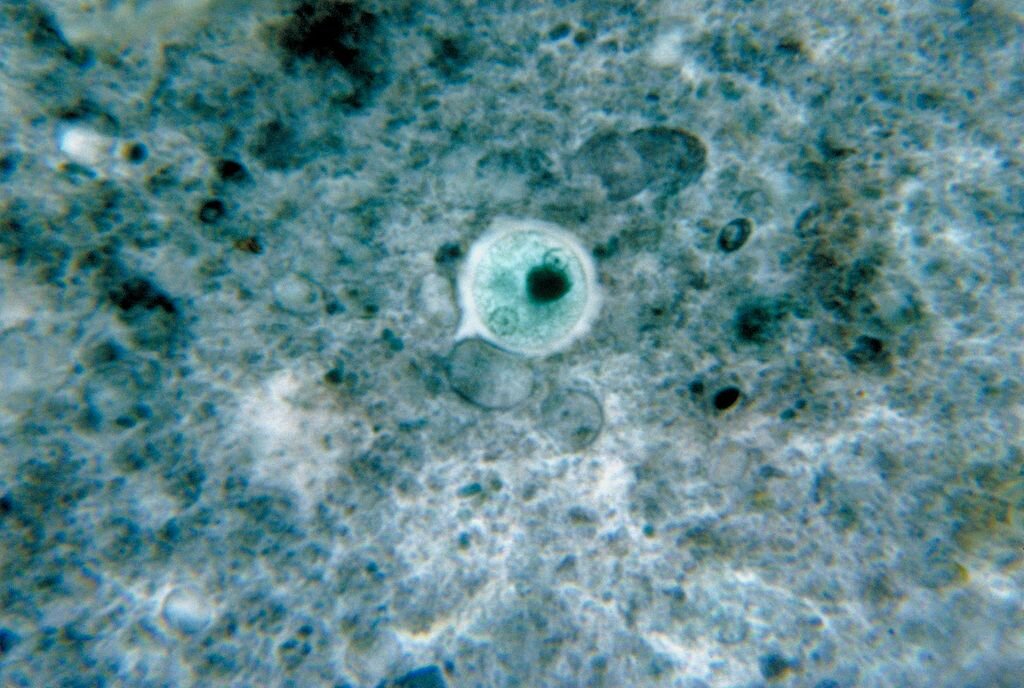

Ten protist to pasożyt zarówno człowieka jak i innych zwierząt stałocieplnych. Szacuje się, że w Polsce zarażonych tym pierwotniakiem jest 60 proc. osób dorosłych. Żywicielami ostatecznymi Toxoplasma gondii są koty, które wydalają zakaźne dla człowieka i innych zwierząt oocysty.

Do zakażenia człowieka dochodzi najczęściej po spożyciu niedogotowanego mięsa zakażonego oocystami lub zanieczyszczonej kocimi odchodami wody, warzyw i owoców. Rzadziej do zakażenia dochodzi na drodze jatrogennej (podczas przeszczepu od zakażonego dawcy) i wertykalnej (od zakażonej matki przez łożysko do płodu). Zarażenie T. gondii może powodować tokoplazmozę nabytą lub wrodzoną. Toksoplazmoza nabyta zazwyczaj przebiega bezobjawowo. Mogą pojawić się objawy grypopodobne (gorączka, bóle mięśni i głowy), a także bóle brzucha, wymioty i biegunka oraz powiększenie węzłów chłonnych. Pasożyt ten jest szczególnie niebezpieczny dla kobiet będących w I trymestrze ciąży, u których może prowadzić do poronienia. Objawy toksoplazmozy wrodzonej pojawiają się w pierwszych miesiącach życia noworodków. Obserwuje się u nich wodogłowie oraz zmiany w gałce ocznej (zapalenie siatkówki i naczyniówki), a także zwapnienie śródmózgowia objawiające się upośledzeniem fizycznym i umysłowym.